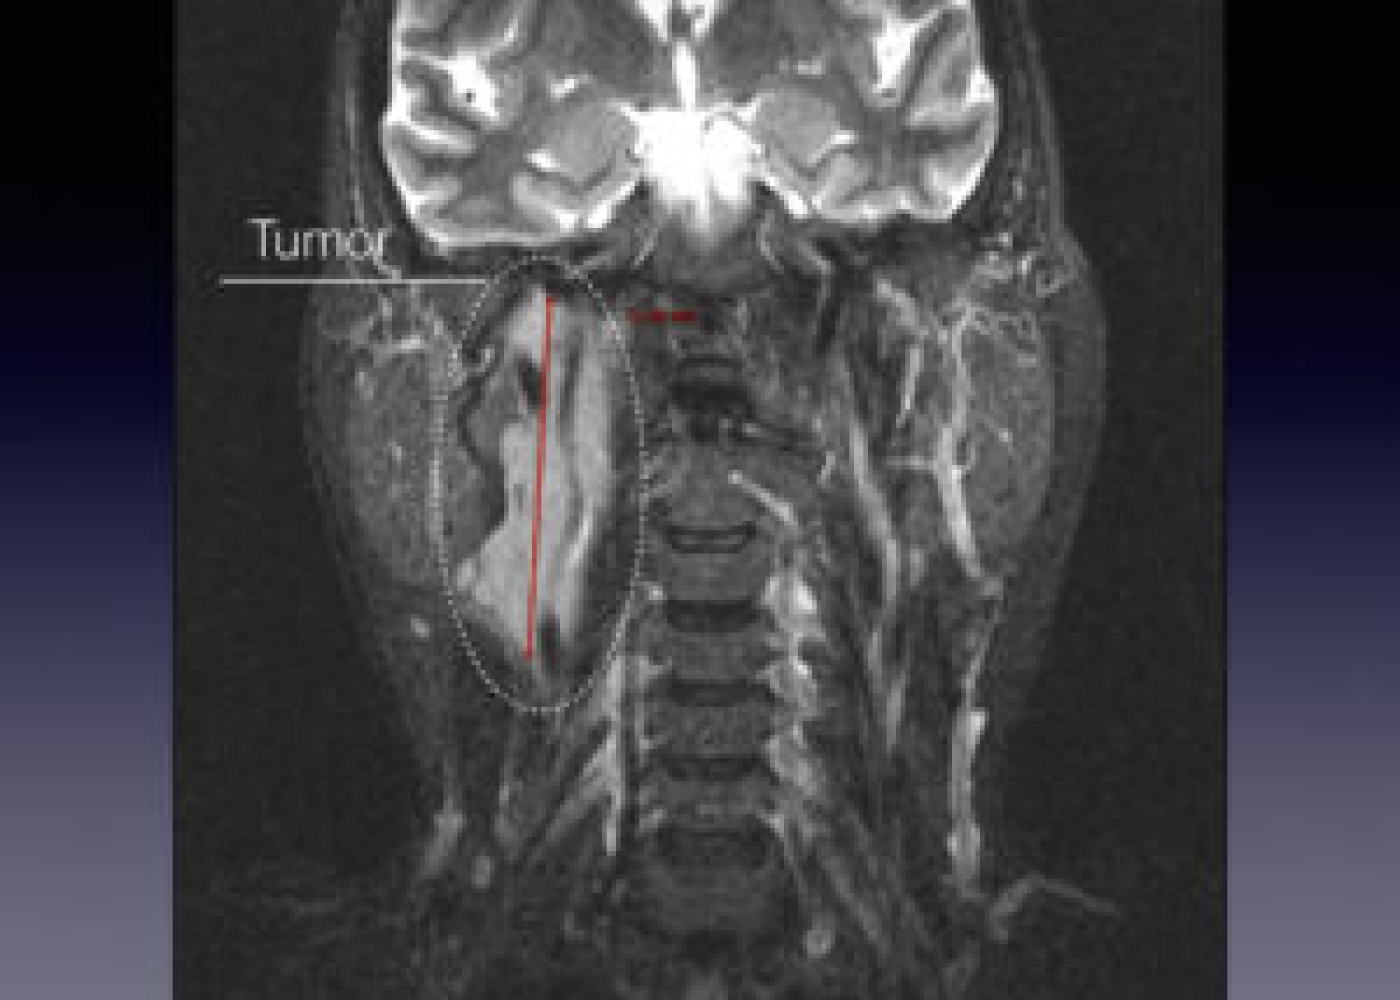

Պացիենտի խոսքով՝ գանգատներն ի հայտ են եկել մոտ 1,5 տարի առաջ և հաջորդիվ գոյացության չափերը զգալի մեծացել են: Հետազոտման ժամանակ աջից պարանոցի քնային եռանկյունում հայտնաբերվել է հստակ սահմաններով մոտ 4սմ տրամագծով անցավ գոյացություն:

Կլինիկոպարակլինիկական հետազոտությունների արդյունքում ախտորոշվել է քնային զարկերակի բիֆուրկացիայի անգիոմիոմատոզ համարտոմա աջից, որը ճնշում էր արտաքին քնային զարկերակը: